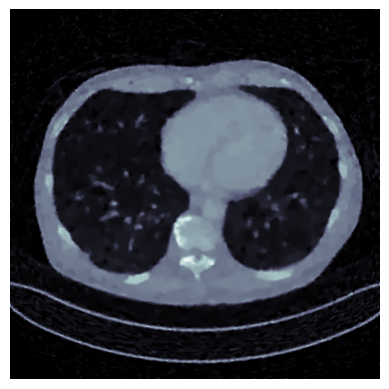

Refer to caption

Ground Truth

Refer to caption31.06

Proposed, 50 iter

Refer to caption26.19

SM-C, 50 iter

Refer to caption26.67

SM-D, 50 iter

Refer to caption21.29

FBP

Refer to caption31.16

Proposed, 500 iter

SM-C, 500 iter

Refer to caption29.06

SM-D, 500 iter

Figure 7: CT: Visual comparison of reconstructions, with PSNR shown at top right corner.